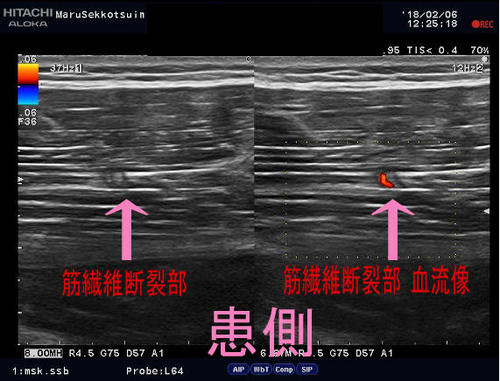

今日の患者さまもサッカー中、

踏み込んだ時に、ふとももの後ろがブチッ!!と痛み、

その直後に歩くのも痛いと御来院。

治療は、しっかり問診、触診、視診を行い、

超音波画像診断装置で患部状態、深さ、広さをしっかり確認し、

早期復帰、回復に向けて対処していきます。